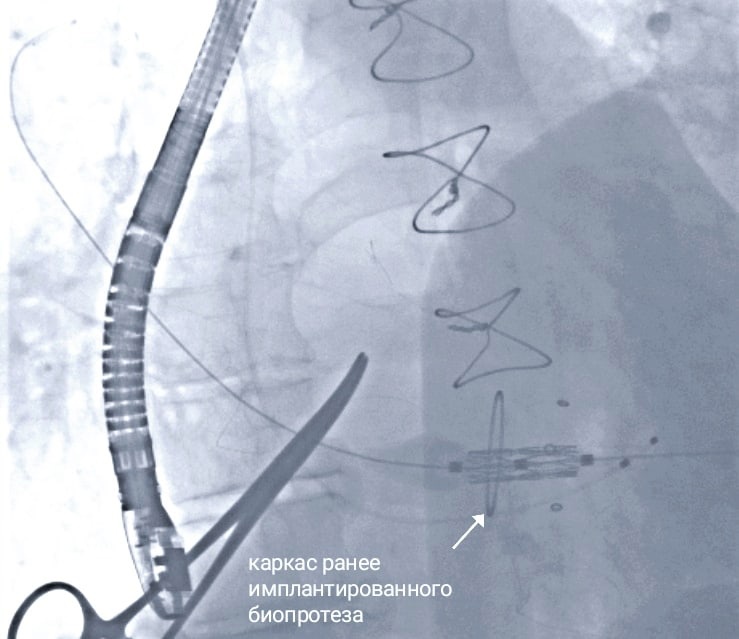

Операцию выполняли в гибридной операционной. Имплантацию клапана кардиохирурги проводили через мини-торакотомию - небольшой разрез в межреберном пространстве. Ввели катетер с протезом, через верхушку левого желудочка сердца установили митральный протез по технологии «клапан-в-клапан». Весь процесс - под контролем чреспищеводной эхокардиографии и рентген-контролем. Операция прошла четко и слаженно.

Пациент – 76 летний житель Калининградской области. В 2013 году он уже перенес большую открытую операцию на сердце в ФЦВМТ - аортокоронарное шунтирование, антиаритмическую процедуру «Лабиринт» и замену митрального клапана сердца биопротезом. Спустя 10 лет вновь обратился к специалистам Центра: беспокоили слабость и одышка. Обследование показало поражение коронарной артерии и дисфункцию биопротеза клапана с признаками жизнеугрожающего митрального стеноза. Врачи провели экстренное стентирование и начали готовить мужчину к плановой операции на клапане.